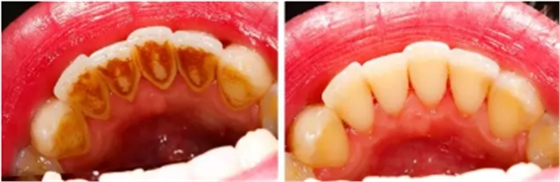

對大多數(shù)人來說,去醫(yī)院潔牙時,牙齒上的牙菌斑基本上已經(jīng)發(fā)展成了牙結(jié)石。牙結(jié)石最容易沉積的部位就是下前牙的舌側(cè)和上后牙的頰側(cè)。定期潔牙的人也會有不同程度的牙結(jié)石堆積,間隔的時間越長,堆積的牙結(jié)石就會越厚越大。

牙結(jié)石首先在牙齒與牙齦的交界處開始沉積,如果堆積的牙結(jié)石沒有及時去除,面積就會越來越大,并朝著牙齦下發(fā)展,導致牙齦炎癥。牙齦炎癥會引起牙齦腫痛,這種腫痛感就像皮膚被針刺一樣。

長時間的牙結(jié)石堆積最后會造成牙槽骨吸收和牙周袋形成,牙周袋內(nèi)很容易聚集食物殘渣和細菌。這樣惡性循環(huán),最后的結(jié)果就是牙齒松動、脫落。

由于不使用牙線、刷牙方法不正確,或者其他因素(如牙列不齊、口腔內(nèi)有不良修復體、藥物作用、激素水平的變化)的影響,也許一個人只有牙齦上的結(jié)石,沒有牙槽骨吸收的現(xiàn)象,此時只需要常規(guī)潔牙。

當牙齦下存在牙結(jié)石,或有牙槽骨吸收跡象時,常規(guī)潔牙往往無法清除牙齦下的結(jié)石,此時需要進行牙周刮治了。

牙槽骨一旦吸收就很難再生,所以,牙周刮治的目的是為了防止進一步的牙槽骨吸收,牙周袋形成以及牙齦出血,利于牙齒穩(wěn)固及健康。

經(jīng)過牙周刮治(包括齦下刮治和根面平整術(shù))的患者,每3到4個月需要進行一次牙周維護,因為他們牙齦下堆積結(jié)石的幾率比一般人要高。同時,掌握正確的刷牙方法(每天至少兩次),每天堅持使用牙線,對維護牙周健康也能起到一定的幫助。